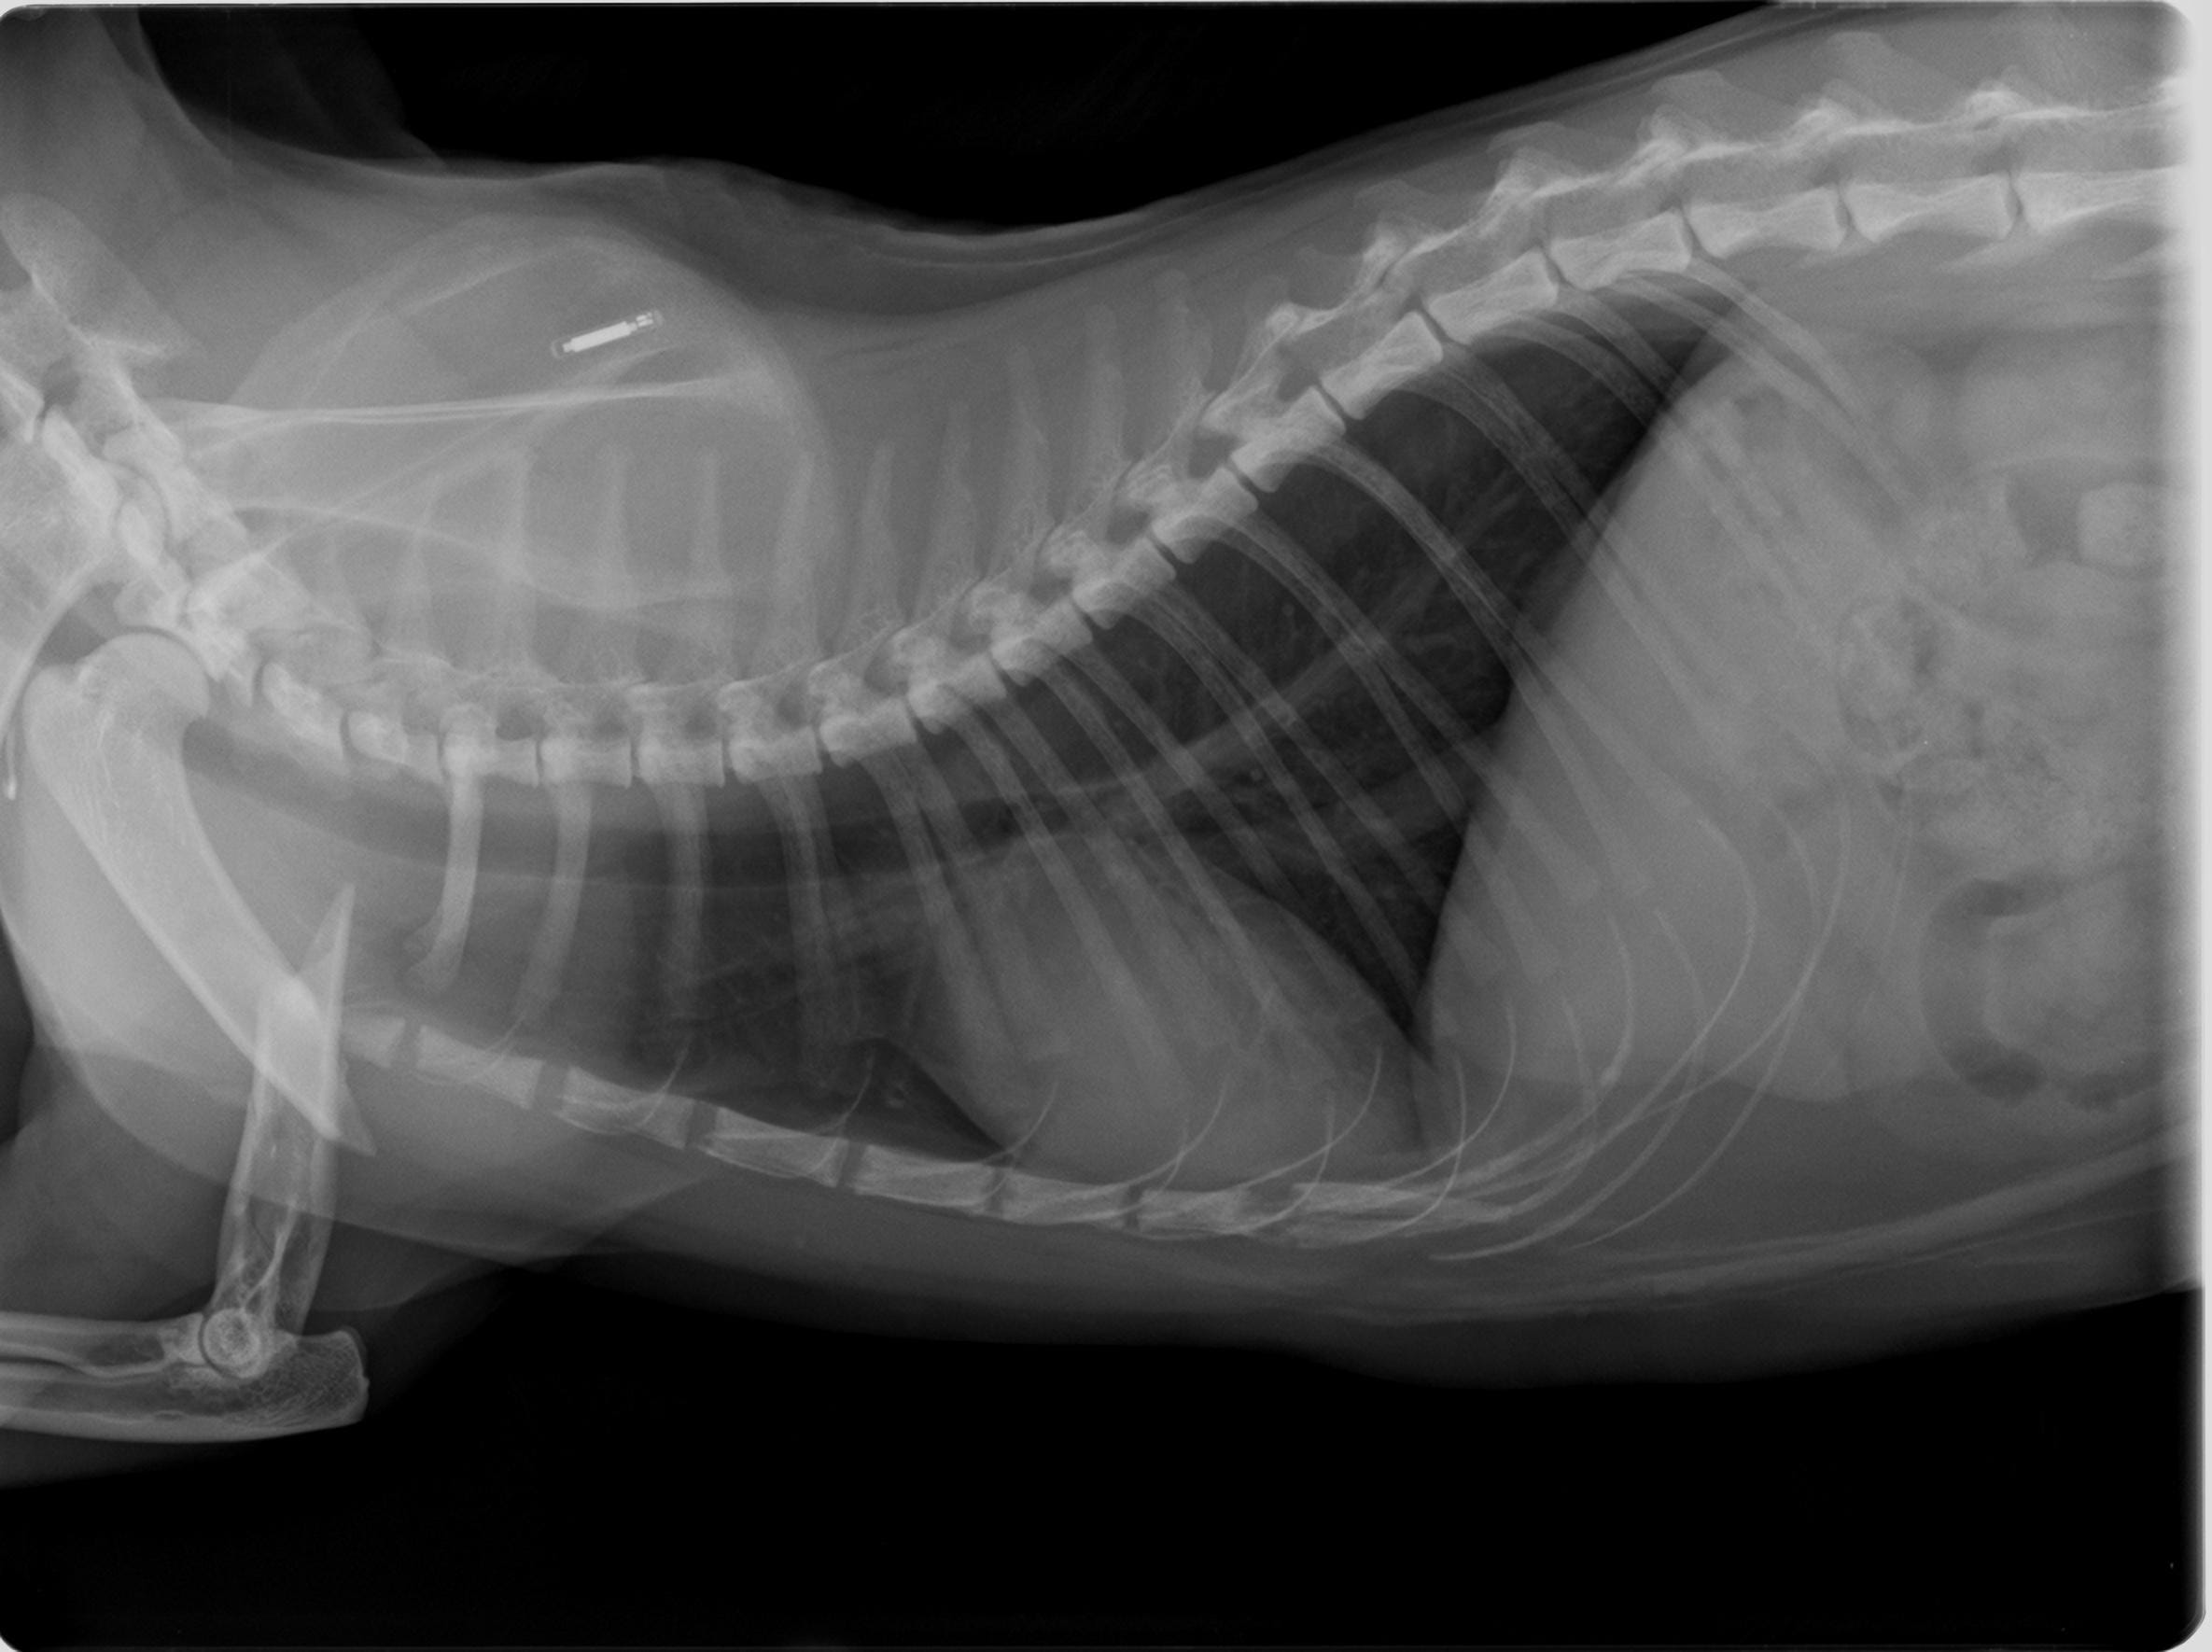

My cat broke her upper right arm a couple of days ago and we dod the surgery (with plates) however is it normal that she is sometimes shaking while trying to sleep, I can tell she is in pain ? Also I am suspecting that her paw might be also broken because she is not stepping on it at all, us it normal? Or it might be also broken but the vet didn’t notice?

Ouch, poor Static! Yes, she may have some pain still. I broke my humerus almost 12 years ago, and I remember how painful it was, even after surgery. I had trouble getting comfortable trying to sleep. If she has pain from the broken humerus, it may hurt to put pressure on her paw because it's putting weight on the leg. It does not mean her paw is broken. You can have her vet x-ray the paw to be safe, and talk to the vet to see if any pain medications might be beneficial to her. I hope this helps!